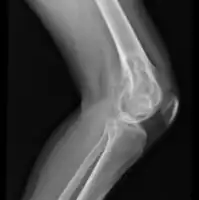

| Osteochondroma[2] | ![]() | |

| Chondroblastoma[2] | ![]() | |